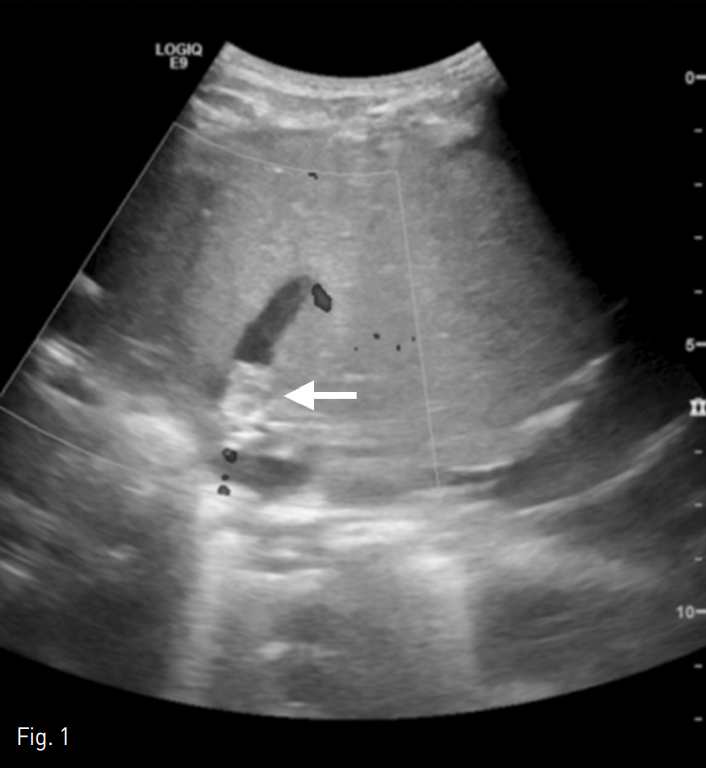

복부 초음파 검사에서 간정맥의 중심 부위에 에코성의 충만결손 병변이 관찰되며 이는 혈전으로 생각되었다. 도플러 검사 상 간 정맥 내의 혈류 신호가 감지되지 않았다 (Fig. 1).

Fig. 1

A Doppler ultrasonography of an 11-month-old male patient revealed no flow signal within the hepatic vein. Note the echogenic filling defect in the central portion of the hepatic vein near the anastomosis site, which is presumed to be a thrombus (arrow).